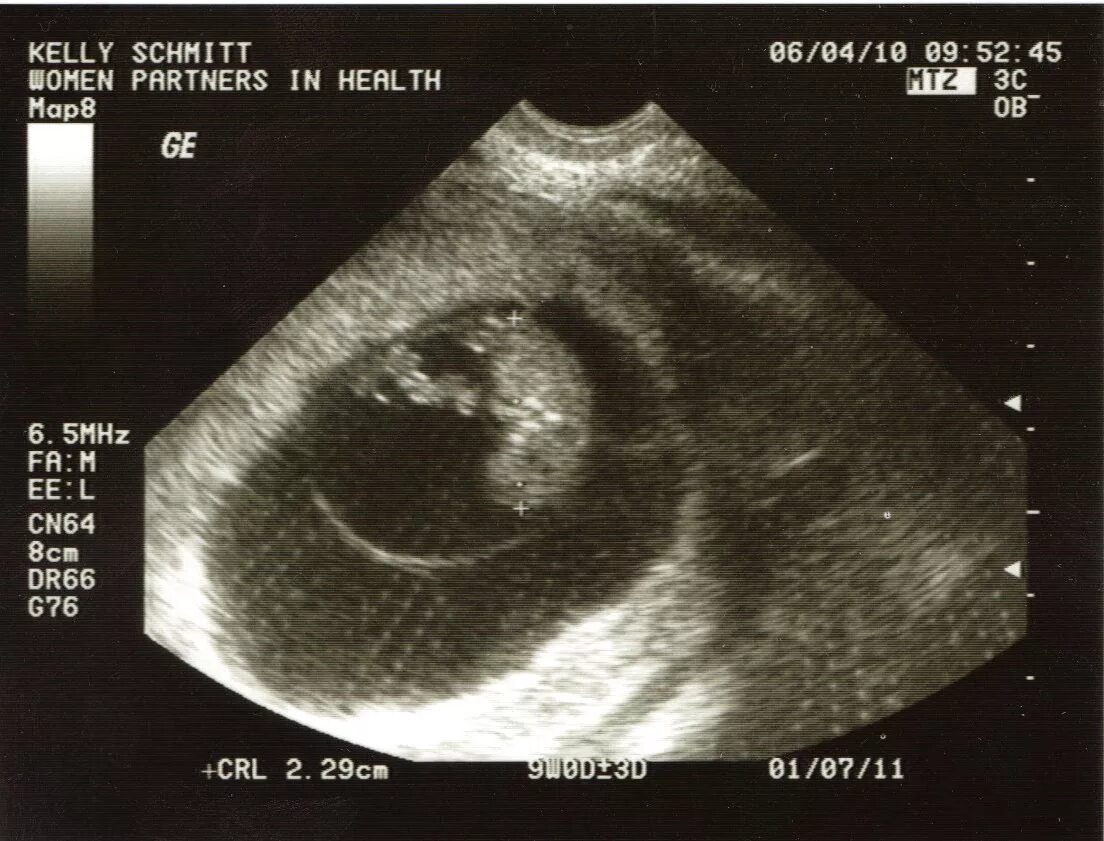

1 9 неделя беременности